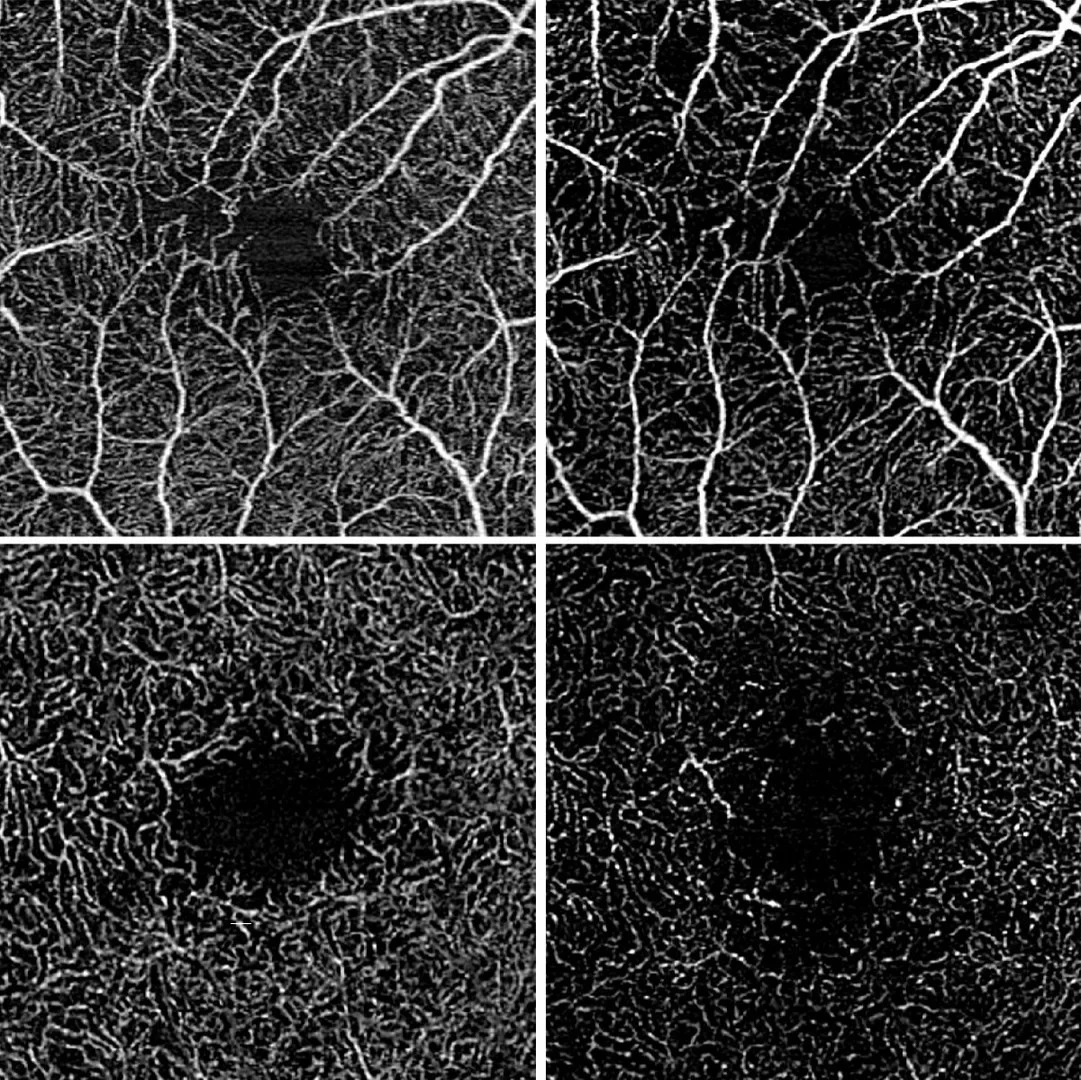

"Optical coherence tomography angiography enables non-contact, non-invasive examination of the retina and the underlying choroid. The retina is scanned successively using harmless, weak laser light, which allows tomographic images of the individual retinal layers to be generated," explains Wintergerst. By comparing several images taken in quick succession, the blood flow can be detected, which allows conclusions to be drawn about the blood supply to the retinal vessels. The researchers from the UKB and the University of Bonn then calculated the blood flow density of the central retina and analyzed how this differs between eyes with stable disease, eyes with an increase in disease activity and eyes with a decrease in disease activity. The researchers examined a total of 52 study participants and were able to show that the blood flow density differed between the three groups examined. An increase in disease activity was associated with a decrease in blood flow density, while a decrease in disease activity was associated with an increase in blood flow density.

In addition, the Bonn researchers used a statistical model, which included over 300 eye examinations, to investigate the predictive power of current blood flow density for the future course of the disease. This showed that a reduced blood flow density was significantly associated with a future deterioration in central visual acuity. "In future, the data obtained could enable us to identify patients with a high risk of disease progression at an earlier stage, for example in order to monitor them particularly closely," says Prof. Dr. Dr. Robert Finger, co-author of the study and now Director of the Eye Clinic at the University Medicine Mannheim (UMM). "We could use this parameter as an endpoint in future randomized clinical trials in order to potentially generate better evidence for the treatment of this rare disease."